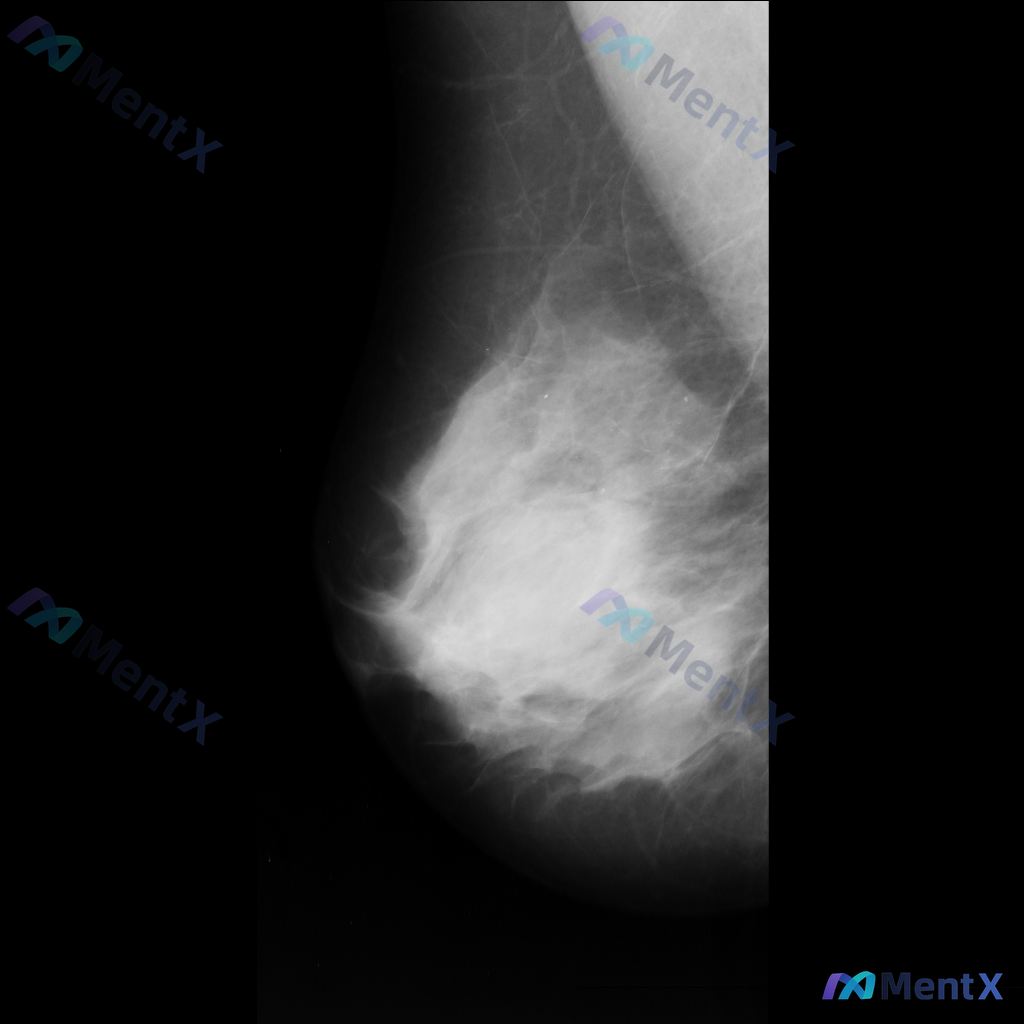

整理了一张乳腺钼靶影像的讨论资料,先和大家分享一下读片描述: 影像可见:不规则、高密度肿块/不对称致密影,伴有毛刺状边缘、结构扭曲和散在钙化。 目前考虑可能存在几种不同的异常方向,想先听听大家的第一反应——单看这组影像特征,你会先往哪种情况考虑? 也可以说说你最关注的是哪一点表现。

整理到一张乳腺钼靶影像资料,主要表现如下: - 乳腺内可见一个较大的肿块,形态不规则,边界部分模糊、呈毛刺状,密度较高,同时伴有明显的结构扭曲; - 另外还存在一枚较小的圆形、边界相对清晰的高密度结节。 想和大家讨论一下:单看目前这组影像表现,你会更倾向哪一种判断方向?